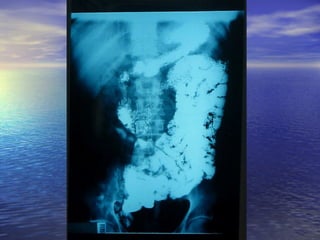

• 1.- CALIBRE: Dilución = obstrucción1.- CALIBRE: Dilución = obstrucción distal, enf.distal, enf.

Celiaca,Celiaca, whipple, linfosarcomawhipple, linfosarcoma

• 2.- ESTENOSIS: Enf. De Crohn, linfosarcoma,2.- ESTENOSIS: Enf. De Crohn, linfosarcoma,

tuberculosis, invasión por tumores cercanostuberculosis, invasión por tumores cercanos

del páncreas, colon.del páncreas, colon.

• 3.- DEFECTOS DE LLENADO: Pólipos ,Sx. Peutz-3.- DEFECTOS DE LLENADO: Pólipos ,Sx. Peutz-

Jegher,Jegher, poliposis familiar, enf. De Crohn, linfomas ypoliposis familiar, enf. De Crohn, linfomas y

metástasis.metástasis.

• 4.- DIVERTICULOSIS: Diverticulosis yeyunal, pseudo-4.- DIVERTICULOSIS: Diverticulosis yeyunal, pseudo-

divertículos (Crohn, esclerosis sistémica)divertículos (Crohn, esclerosis sistémica)